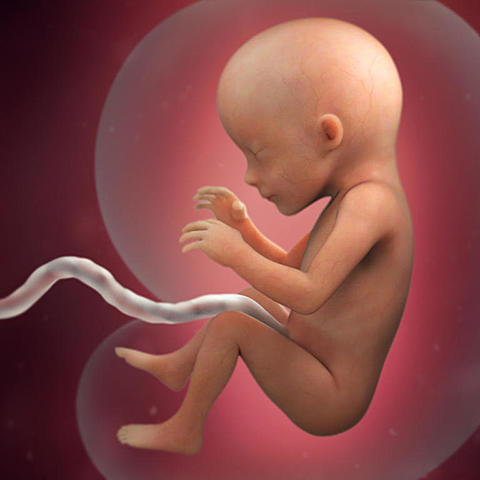

• Semana 10

10

Semana 10

-Se deja de usar la palabra embrión para denominarlo feto.

-Las medidas del feto rondan los 4 centímetros y su peso los 5 gramos.

-Se desarrollan parpados, orejas y cara.

• Semana 11

11

Semana 11

-Pesa aproximadamente 8 gramos y mide entre 4 y 6 centímetros.

-Sus dedos están ya separados.

-Las membranas que los unían desaparece.

-Las orejas migran a su posición definitiva.

-Ya puede abrir y cerrar sus manos.